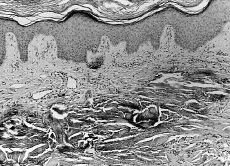

Se efectuó una biopsia cutánea en la que se observa una epidermis sin alteraciones, mientras que a nivel de la dermis media los haces colágenos estaban impregnados de sales de calcio, hallándose algunos histiocitos entre esas fibras calcificadas (Fig. 2).

FIG. 2.--A: Panorámica histológica que muestra la extensa calcificación sobre las fibras de colágeno dérmico. B: Detalle histológico en el que se observa el depósito de calcio, así como acúmulos histiocitarios entre los haces.